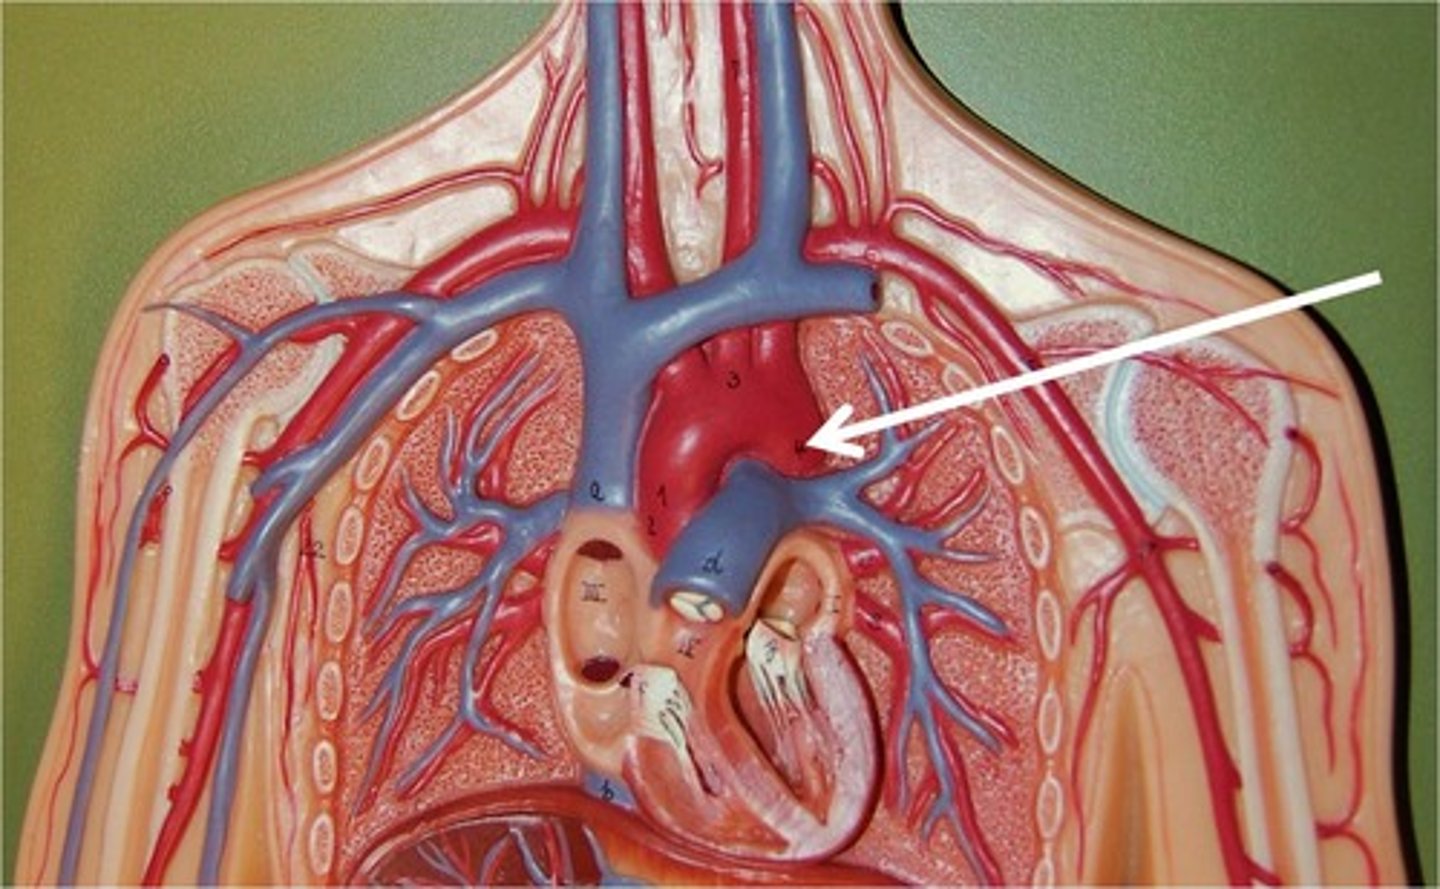

superior vena cava

the vena cava drain into the right atrium

posterior side, upper part

ascending aorta

right and left coronary arteries branch from here (portion)

arch of the aorta

curved part of aorta

brachiocephalic artery

first branch off aortic arch

right common carotid artery

branches off brachiocephalic artery

supplies blood to right side of head and neck

right subclavian artery

passes to the upper limb, deep to the clavicle